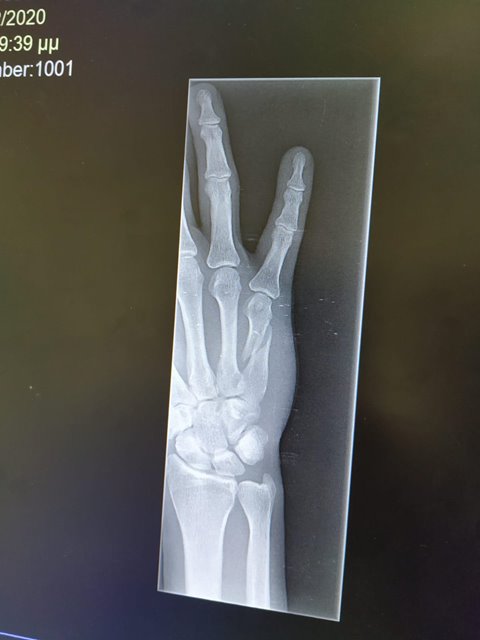

Pád v rychlé technické sekci znamenal propad na celkové třetí místo. Co je ale mnohem podstatnější, následné vyšetření v nemocnici v Aténách potvrdilo zlomeninu pátého metacarpu pravé ruky.

„Po repozici ta ruka vypadá dobře. Musíme ale zvážit, zda kost nezpevníme dlahou s ohledem na délku hojení a urychlení návratu Honzy zpět do závodů,“ vysvětluje MUDr. Jan Kryl, člen lékařského týmu Reprezentace MTB.